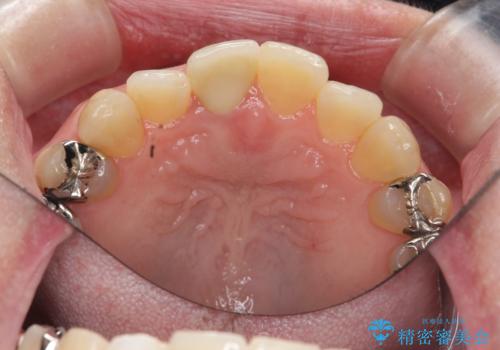

- 十数年前に治療した前歯のクラウンの歯ぐきの位置が変化し、黒いラインが見え審美性の改善を求めて来院されました。

ファイバーコアのやりかえを行ったのち、金属を用いないジルコニアクラウンによる再補綴を行い前歯の審美性の向上を計画します。

近年前歯のクラウン製作に用いられるジルコニアクラウンは、金属を用いていないため経年的に歯ぐきの位置が変わっても黒いラインが見えることなく審美性の意地が期待できます。